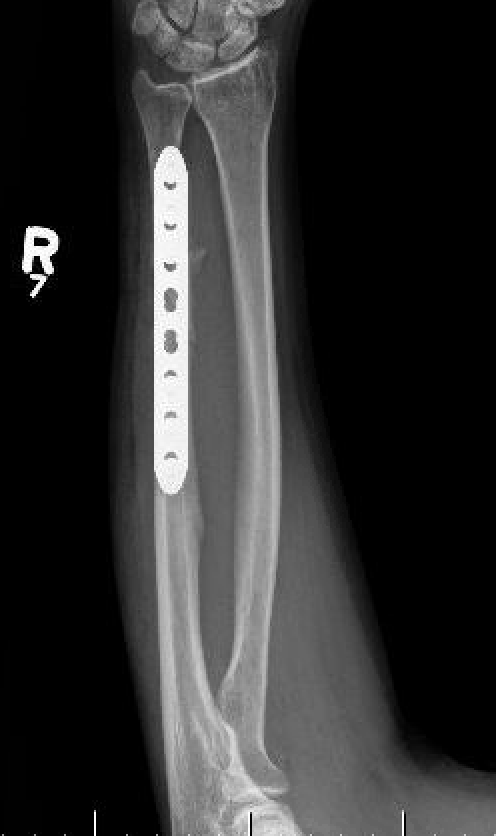

Options

Compression plating

Technique